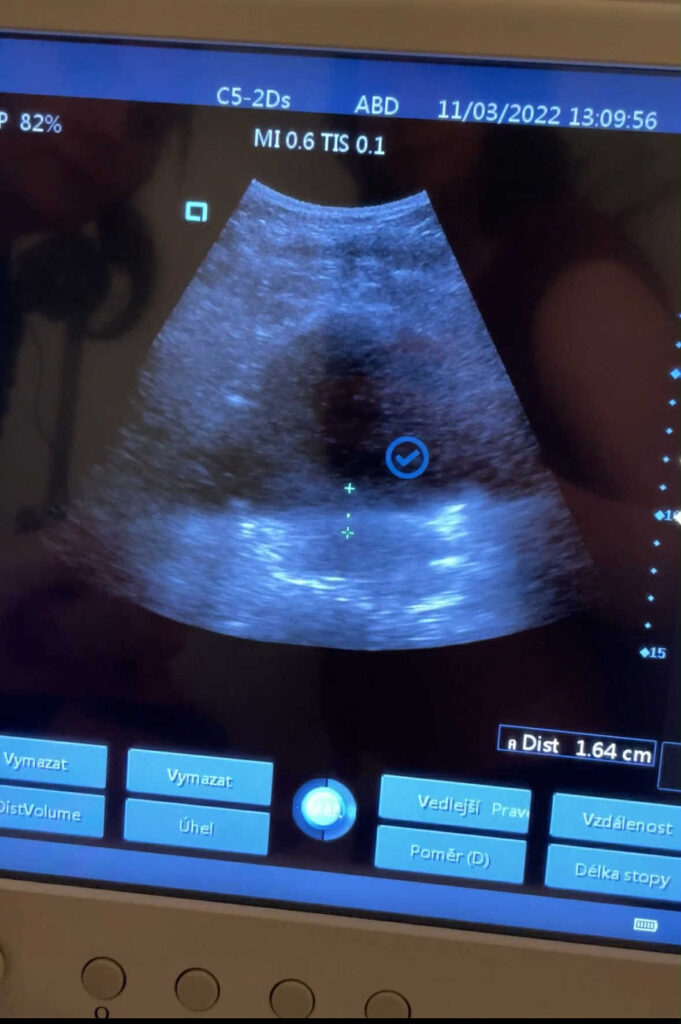

V REHABE využíváme moderní ultrazvukovou diagnostiku, která nám umožňuje přesně zhodnotit stav vašeho pánevního dna a sledovat jeho aktivaci v reálném čase.

„Ultrazvuk poskytuje okamžitou zpětnou vazbu – žena přímo vidí, jak její pánevní dno pracuje,“ říká Gabča. „To je neocenitelné pro správné pochopení cvičení. Když žena vidí na obrazovce, že to dělá správně, mnohem rychleji se to naučí.“

Při vyšetření změříme sílu a funkčnost vašeho pánevního dna, zjistíme, zda ho dokážete správně aktivovat, a navrhneme individuální terapeutický plán.